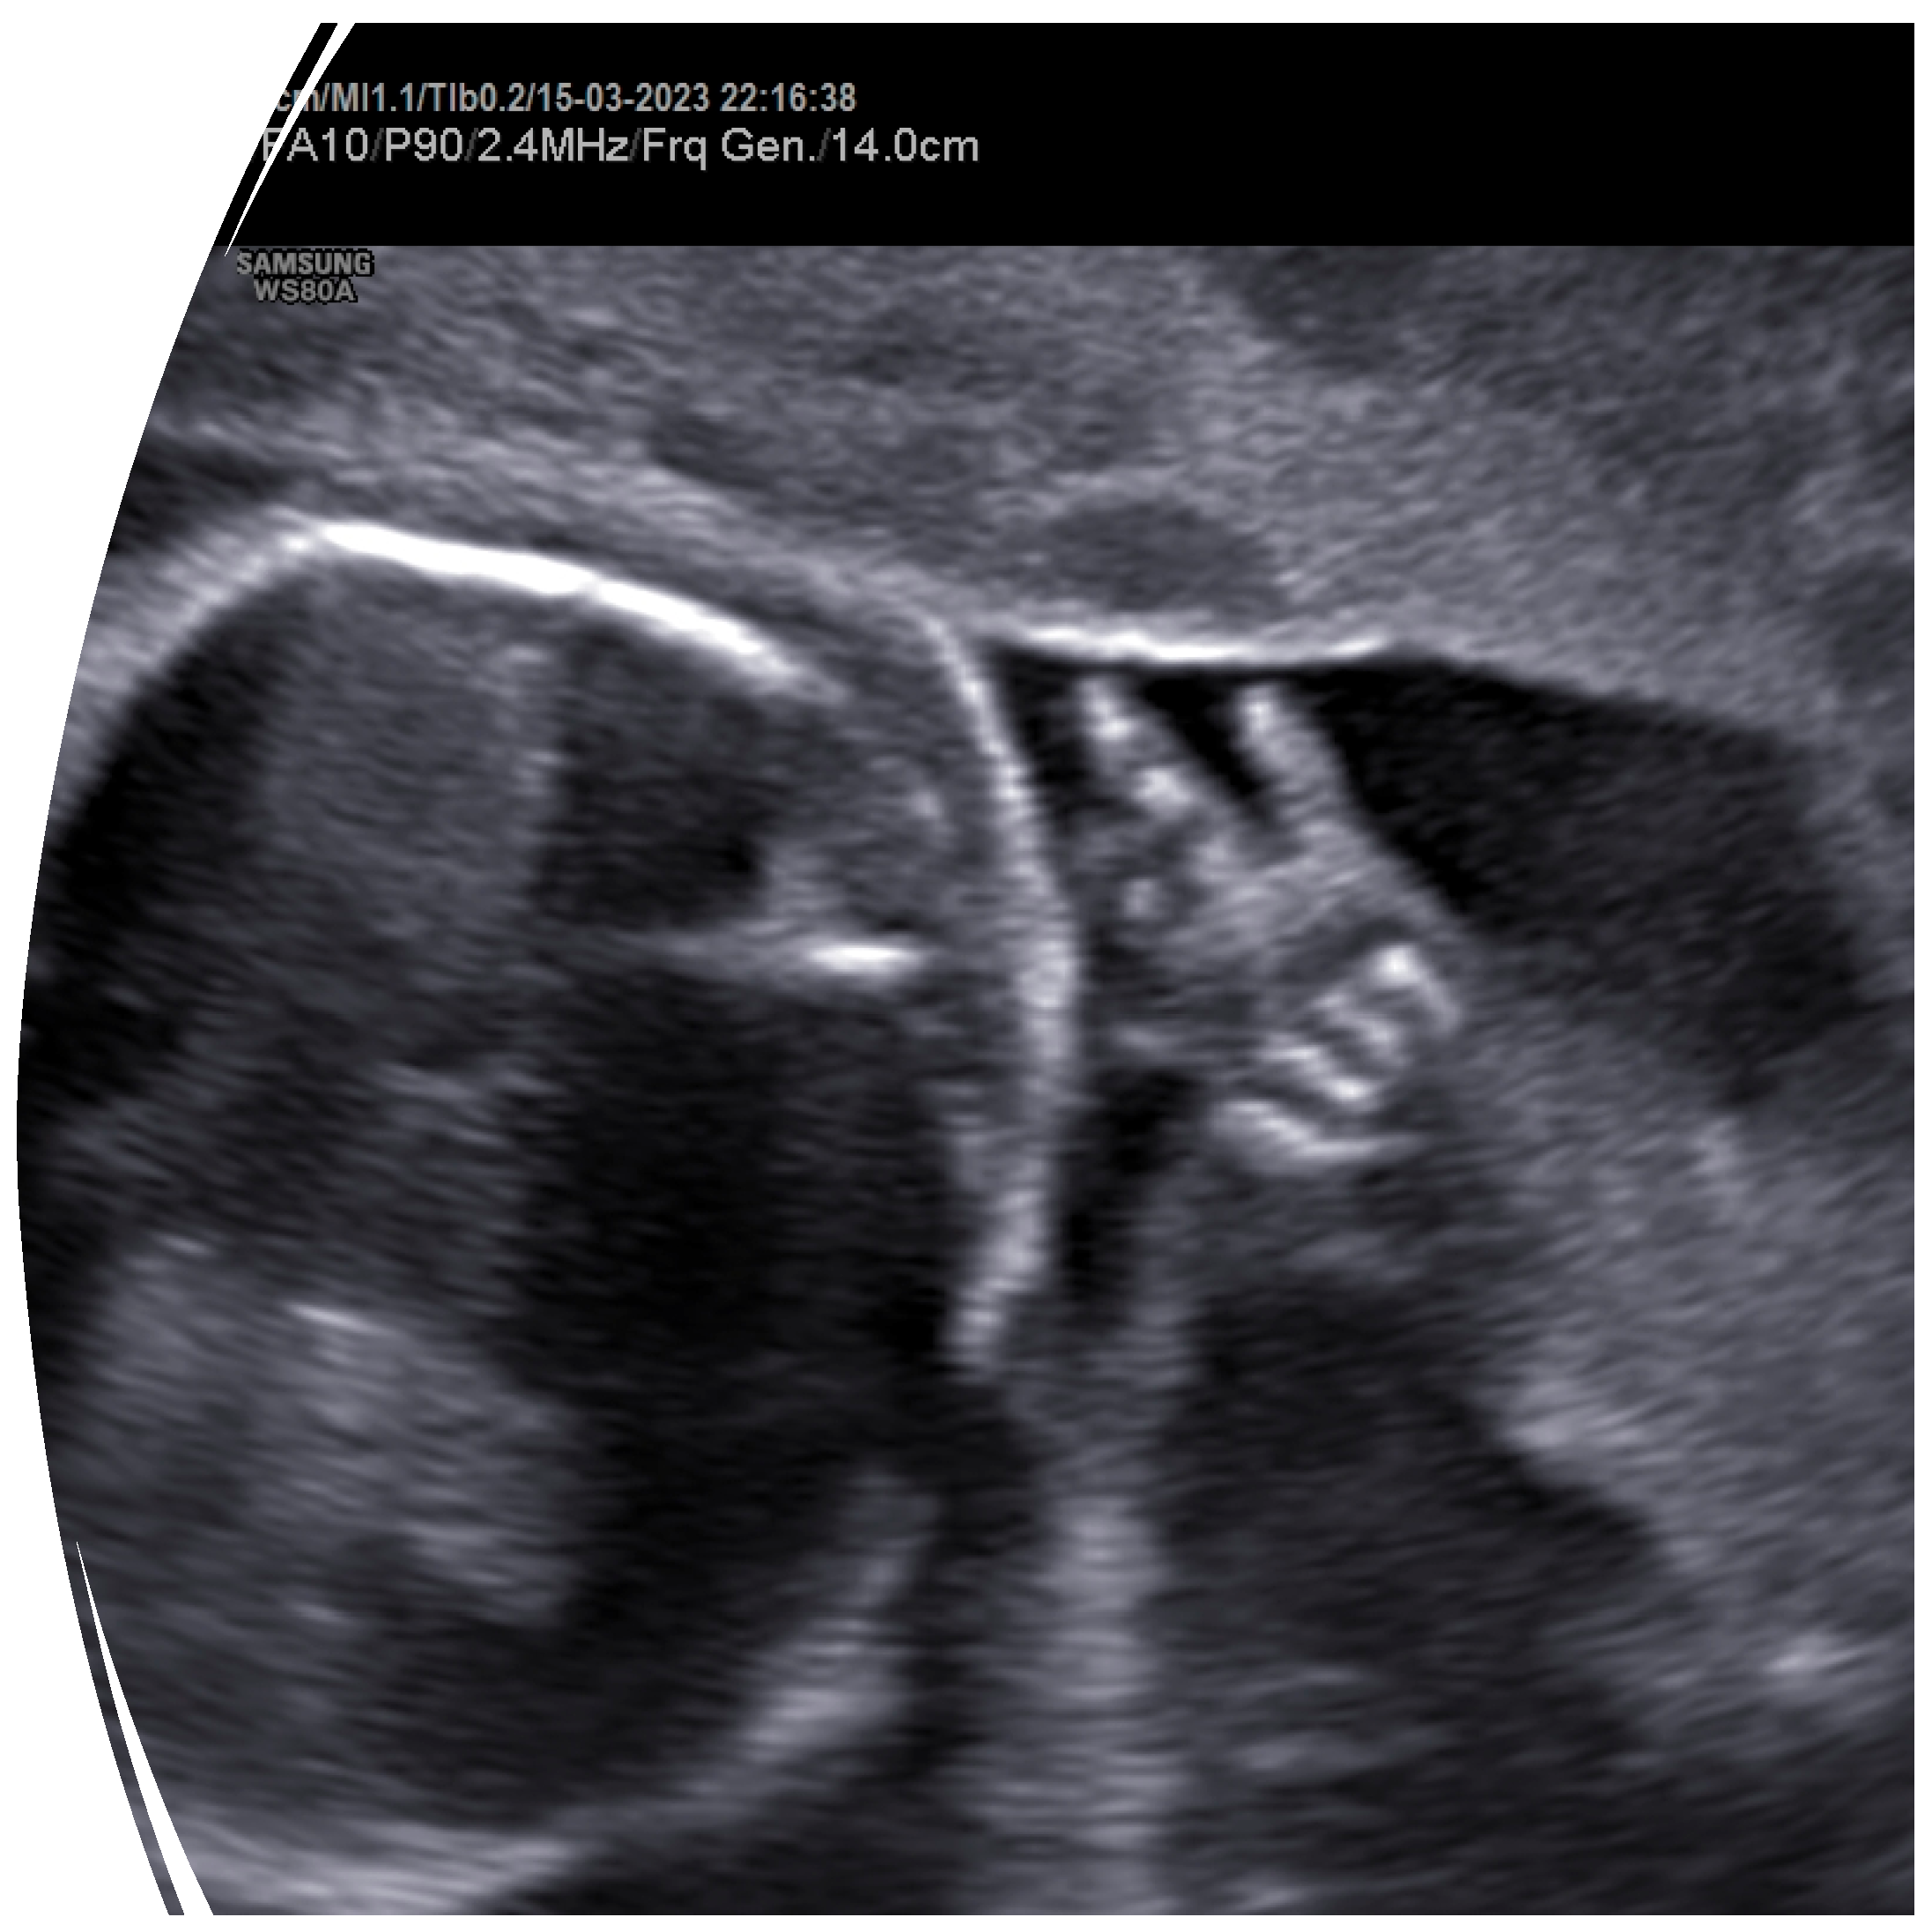

2. Case Presentation